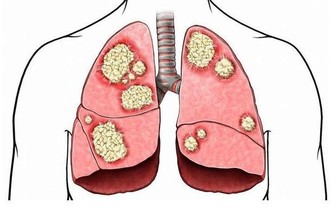

近年來癌症的發生逐漸年輕化,每年都有大量的年輕人被確診為癌症。很多腫瘤專科的大夫在臨床上深有體會,尤其是胃癌、肺癌、腸癌等常見癌症更是如此。

隨著科普保健,大家也都明白癌症的發生不是單一的因素導致的,可能與各個方面都有關係,比如過分的勞累、生活作息不規律等。

但是,消化道腫瘤發病的年輕化,一定是與飲食有很大的相關性。